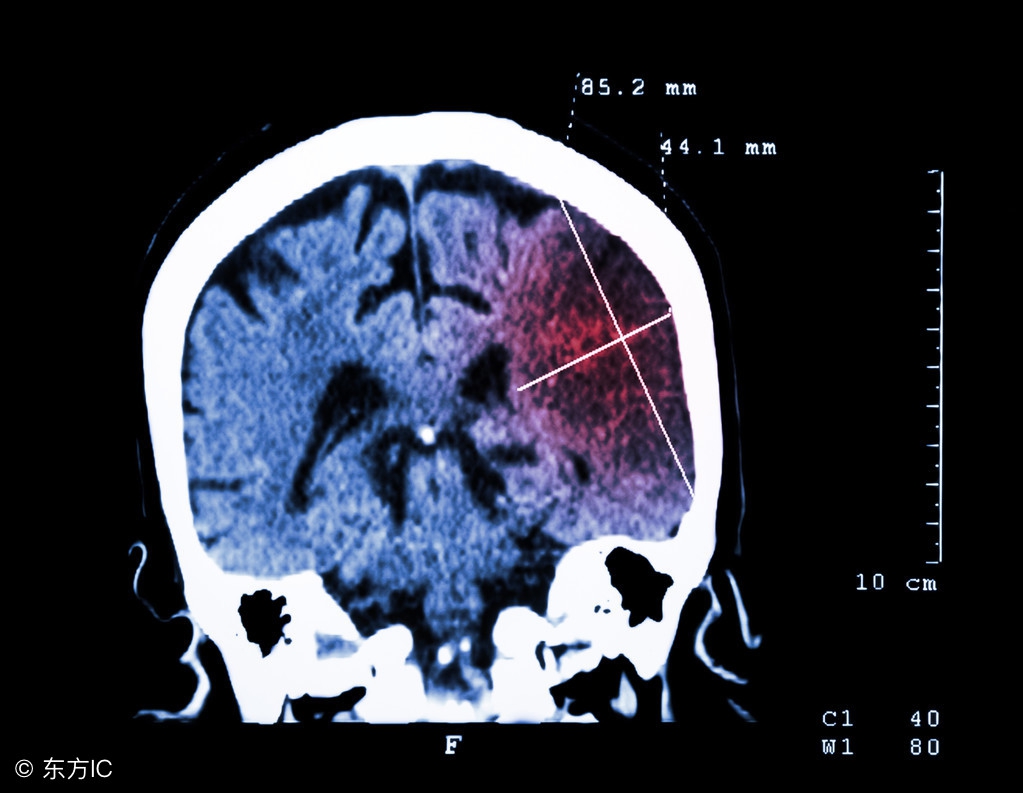

脑梗塞是一种较为常见的疾病,该疾病的发病给患者、家庭及社会带来极大的痛苦和沉重的负担。我们大家在日常生活中一定要对脑梗塞典型症状表现多加了解,在出现该疾病的症状时,尽早到正规医院进行诊断,确诊后积极配合医生治疗,只有这样才能避免病情加重。以下是相关内容介绍。

脑梗塞可发生于任何年龄,以青壮年多见。多在活动中急性发病,无前驱症状,局灶性神经体征在数秒至数分钟达到高峰,多表现为完全性卒中,意识清楚或轻度意识模糊,颈内动脉或大脑中动脉主干栓塞导致大面积脑梗塞,可发生严重脑水肿、颅内压增高,甚至脑疝和昏迷,脑梗塞的表现常见痫性发作;椎-基底动脉系统栓塞常发生昏迷。个别病例局灶性体征稳定或一度好转后又出现加重提示栓塞再发或继发出血。

脑梗塞患者主诉多为面瘫、上肢单瘫、偏瘫、失语、抽搐等症状。偏瘫以面和上肢为重,下肢相对较轻。感觉和视觉可能有轻度影响,但一般不明显。抽搐大多数为局限性,如为全身性大发作,则提示栓塞范围广泛,脑梗塞病情较重,约有1/5的脑梗塞患者出现眩晕、复视、共济失调、交叉性瘫痪等症状。